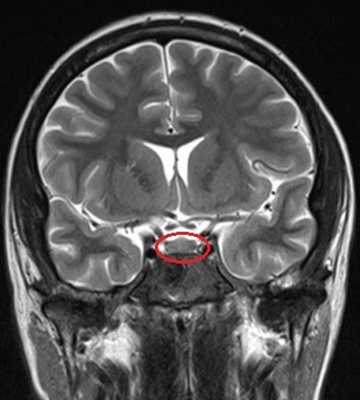

МРТ гипофиза (обведено) без контраста и с с контрастом. В норме гипофиз равномерно накапливает контрастное вещество — становится светлым.